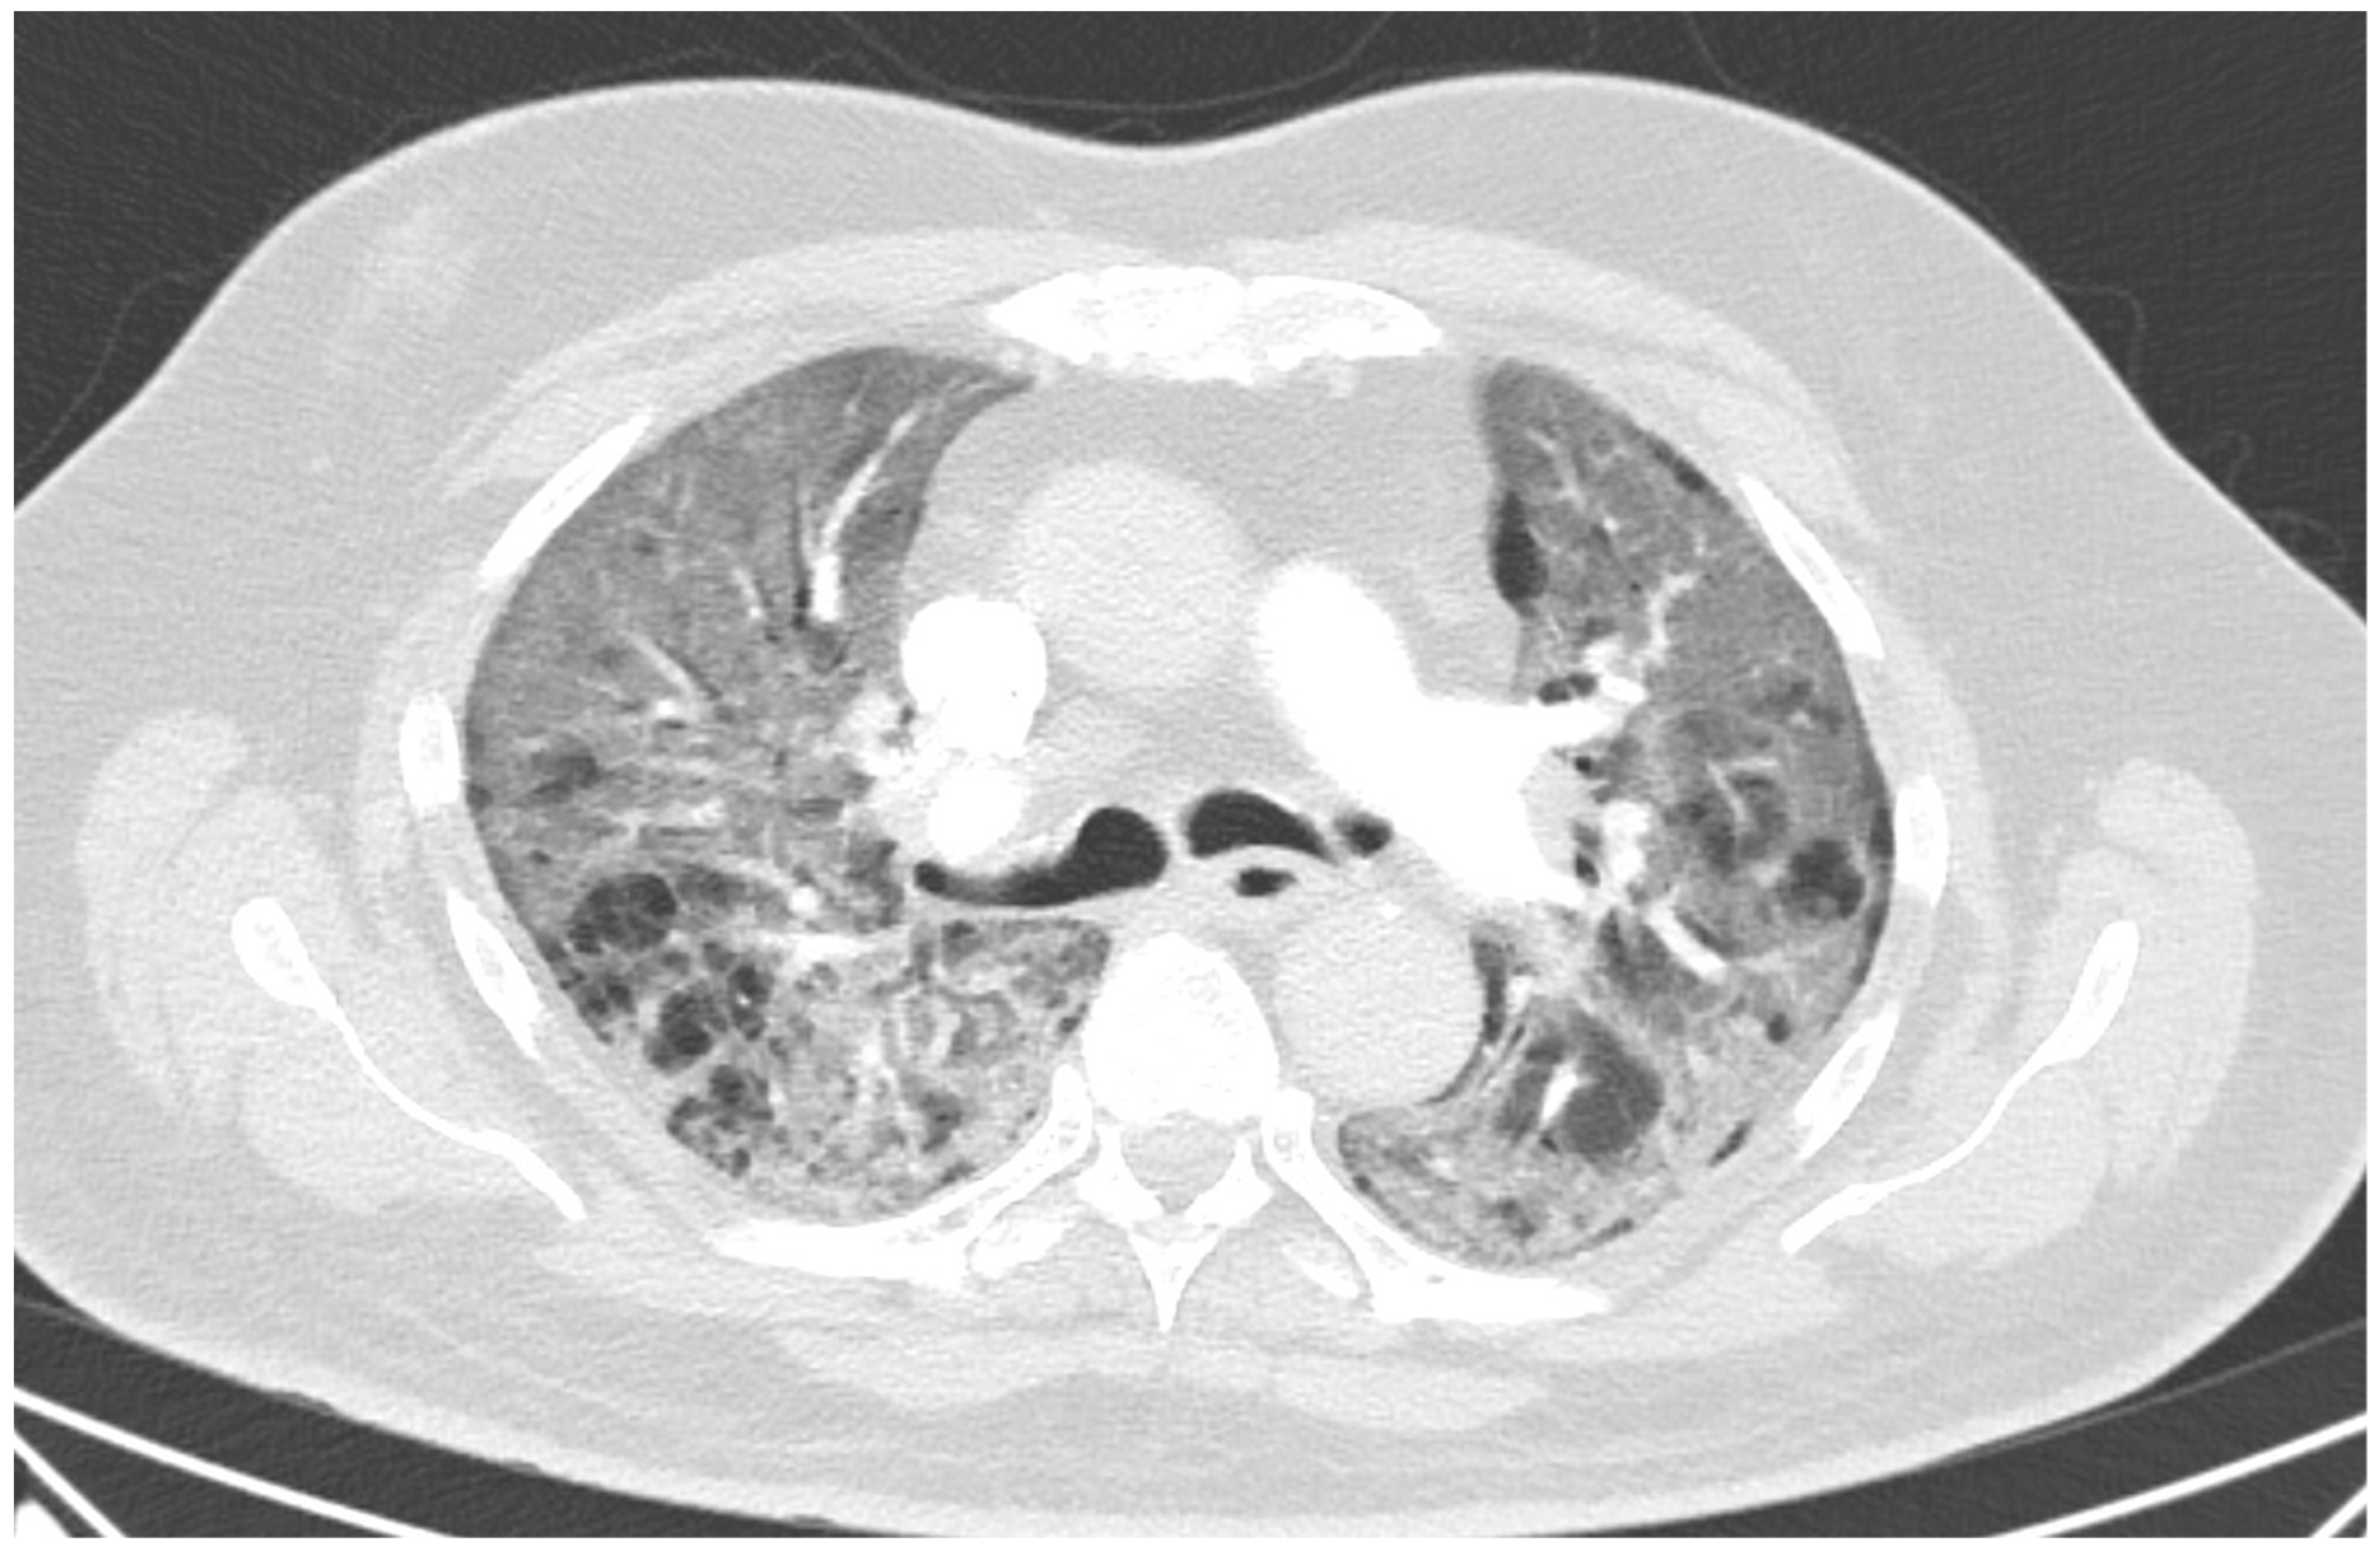

Figure 1.

Lung CT on day 11 showing multifocal ground-glass opacities with crazy paving signs bilaterally.

A 60 year old male smoker with a history of arterial hypertension and myocardial infarction developed typical COVID-19 symptoms in April 2021—cough, exertional dyspnoea, chest tightness, and fever. Developing prior to the widespread availability of antiCOVID-19 vaccines, he was unvaccinated. Four days after the onset of symptoms, he was admitted to the Pulmonary Department of the University Hospital Brno due to the worsening dyspnoea. He tested positive for SARS-CoV-2. The exact viral variant was not identified. The predominant variant in the Czech population was B.1.1.7 (Alpha) at that time. His initial chest X-ray revealed diffuse lung infiltrates, especially in the right upper-middle quadrant. Despite receiving standard treatment with remdesivir for five days, corticosteroids (methylprednisolone 80 mg intravenously per day), and a prophylactic dose of low-molecular-weight heparin (LMWH), his dyspnoea worsened. Hence, supplemental oxygen and antibiotics (i.e., clarithromycin 500 mg IV BID and ceftriaxone 2 g IV BID for 5 days) were administered. Due to the progressively increasing levels of D-Dimers in laboratory tests, CT angiography was performed, showing typical findings consistent with COVID-19 pneumonia of diffuse lung parenchyma involvement without any signs of pulmonary embolism (Figure 1). The patient’s oxygen was gradually increased to achieve a peripheral blood saturation of >90%. On day 11, the patient was transferred to the ICU after his saturation dropped to 50–60% despite an oxygen flow via face mask of approximately 15 litres per minute. High-flow oxygen therapy (HFOT) with awake prone positioning was commenced, and corticosteroids were switched from methylprednisolone 80 mg to dexamethasone 6 mg IV per day. Despite ten days of corticosteroid administration, the patient’s clinical condition began to deteriorate significantly, and his hypoxaemia worsened. On day 12, he was intubated and placed on invasive ventilation with aggressive parameters (positive end-expiratory pressure: 12 cm H2O; fraction of oxygen: 80%). Bronchoalveolar lavage (BAL) was performed with the PCR testing showing more than 2 million copies of SARS-CoV-2 per millilitre (a significant number); no fungal DNA was detected at this time. As the patient became anuric, daily dialysis treatment commenced on day 13. Ventilator-associated pneumonia (VAP) caused by Klebsiella pneumoniae producing extended-spectrum beta-lactamase (ESBL) was confirmed by BAL fluid cultivation, and meropenem 2 g per day in continuous infusion was started. Serum levels of cardiac markers were elevated (troponin T: 67 ng/L; NT pro Brain Natriuretic Peptide (NTproBNP): 3892 ng/L), indicating advancing myocardial injury. Norepinephrine infusion was needed to achieve adequate blood pressure. The capillary refill time was prolonged over 2 s, consistent with circulatory dysfunction. A day later, the patient developed atrial fibrillation and hemodynamic instability with doses of norepinephrine up to 0.5 µg/kg/min. On day 16, a tracheostomy was performed, while the ventilation remained fully controlled with a P/F (PaO2/inspiration fraction of O2) index below 150. Two days later, the progression of circulatory dysfunction became apparent, accompanied by an elevation of inflammatory markers. Follow-up BAL was performed, empirical vancomycin was added on day 19, and doses were adjusted respecting dialysis procedures. Abdominal ultrasound revealed no clear site of a new infection. Blood cultures were negative, and BAL showed more than 3 million copies of SARS-CoV-2 and 1200 copies of Cryptococcus neoformans per millilitre/BAL. Serum panfungal antigen ((1,3)-β-glucan D) and serum cryptococcal antigen (i.e., glucuronoxylomannan) levels were negative. Over the next four days, organ dysfunction slightly improved; therefore, the patient was slowly weaned-off sedation, and the mode of ventilation was switched to pressure support. On day 21, vancomycin was switched to linezolid 600 mg IV BID. On day 22, a follow-up BAL was performed. PCR showed borderline positivity for Cryptococcus neoformans (300 copies per millilitre), and serum positivity for cryptococcal antigen was detected. Combined antifungal therapy with liposomal amphotericin B (Abelcet) 500 mg IV per day and fluconazole 800 mg IV per day was commenced. Blood cultures were negative for bacteria and fungi. Cerebrospinal fluid analysis, including PCR, ruled out CNS dissemination. On day 24, the patient’s circulatory instability progressed rapidly with no response to vasopressors and inotropes, which led to a subsequent cardiac arrest followed by unsuccessful cardiopulmonary resuscitation (CPR). Multiorgan dysfunction caused by COVID-19 infection and cryptococcal pneumonia was stated as the primary cause of death from a clinician’s perspective. The most significant feature during the histopathological examination was the severe diffuse alveolar damage (DAD) (Figure 2), specifically its exudative/proliferative stage, due to the prolonged period of COVID-19 pneumonia. In addition, a considerable number of dispersed intra-alveolar microorganisms, with a thick mucus capsule, were found in the lung parenchyma (Figure 3). These microorganisms (variably sized: approximately 7–20 μm) stained with both Alcian blue (Figure 4) and Giemsa (Figure 5). There was only a very subtle inflammatory reaction in the surrounding tissue, mostly lymphocytic. A post-mortem lung smear was microbiologically tested and returned positive for Cryptococcus neoformans. Thus, we consider secondary lung cryptococcosis as proven. Respiratory failure as a result of DAD was the immediate cause of death of the patient.